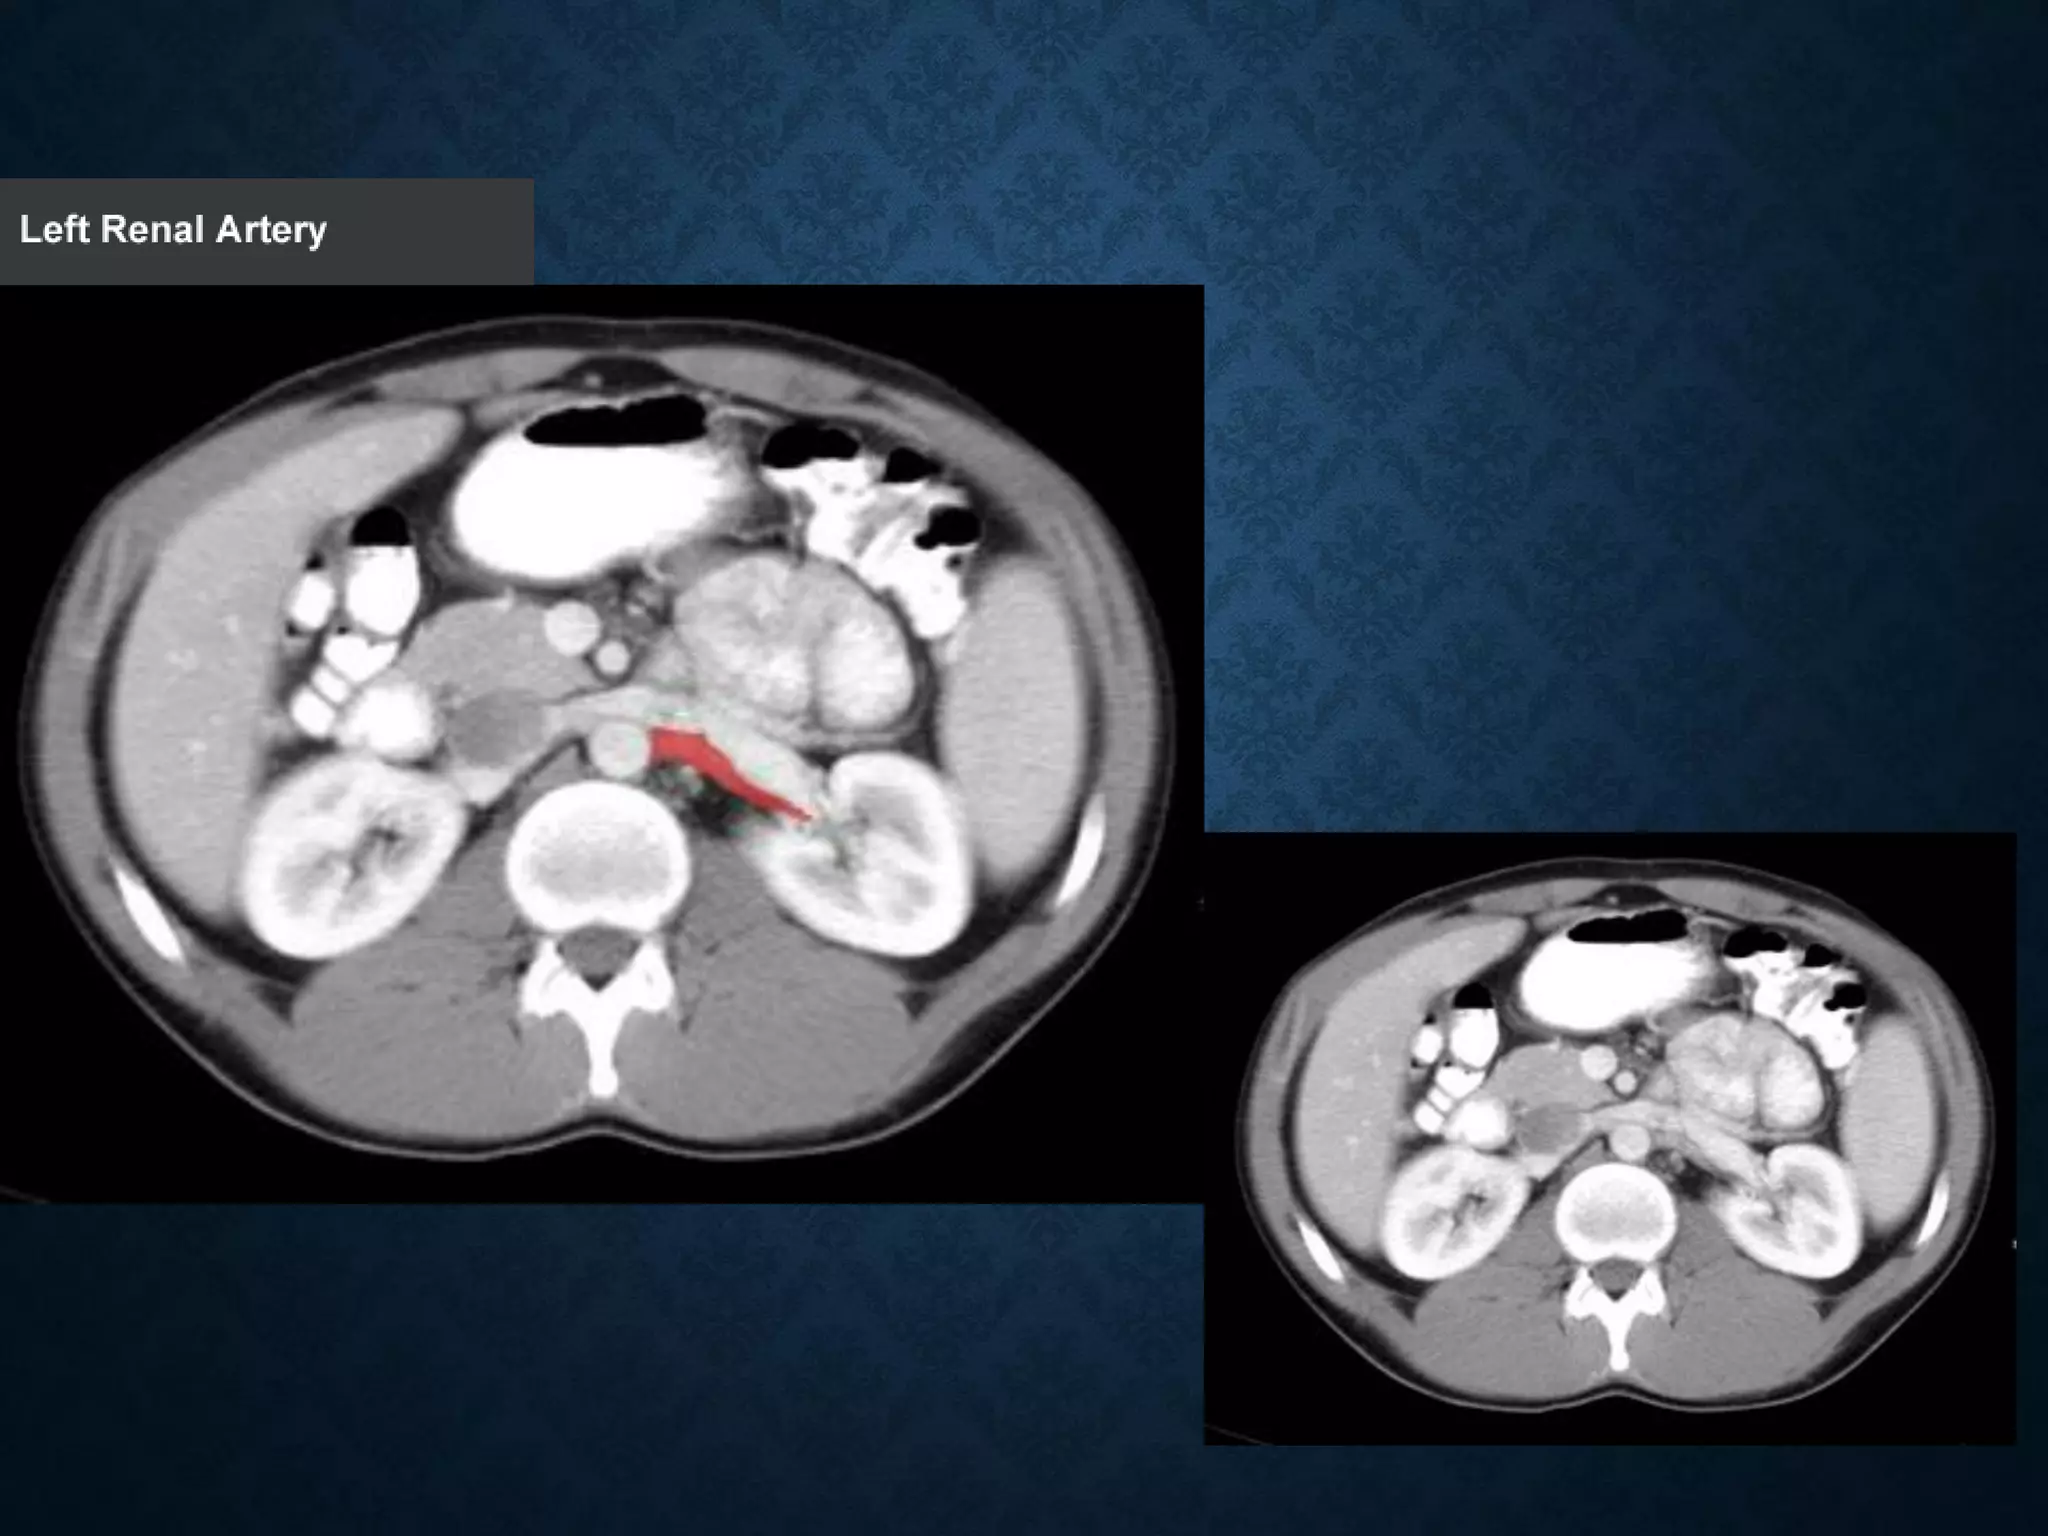

Identify the following structures in the body CT to the right. To view the location of the structure in the image click on

the label at the left and the structure will be indicated in the image. Abdominal CT scans typically begin just above

the diaphragm, so the first slice you see is of the lower chest.

Identify the followingstructures in the body CT to the right. To view the location of the structure in the image click on the label at the left and the structure will be indicated in the image. Abdominal CT scans typically begin just above the diaphragm, so the first slice you see is of the lower chest.